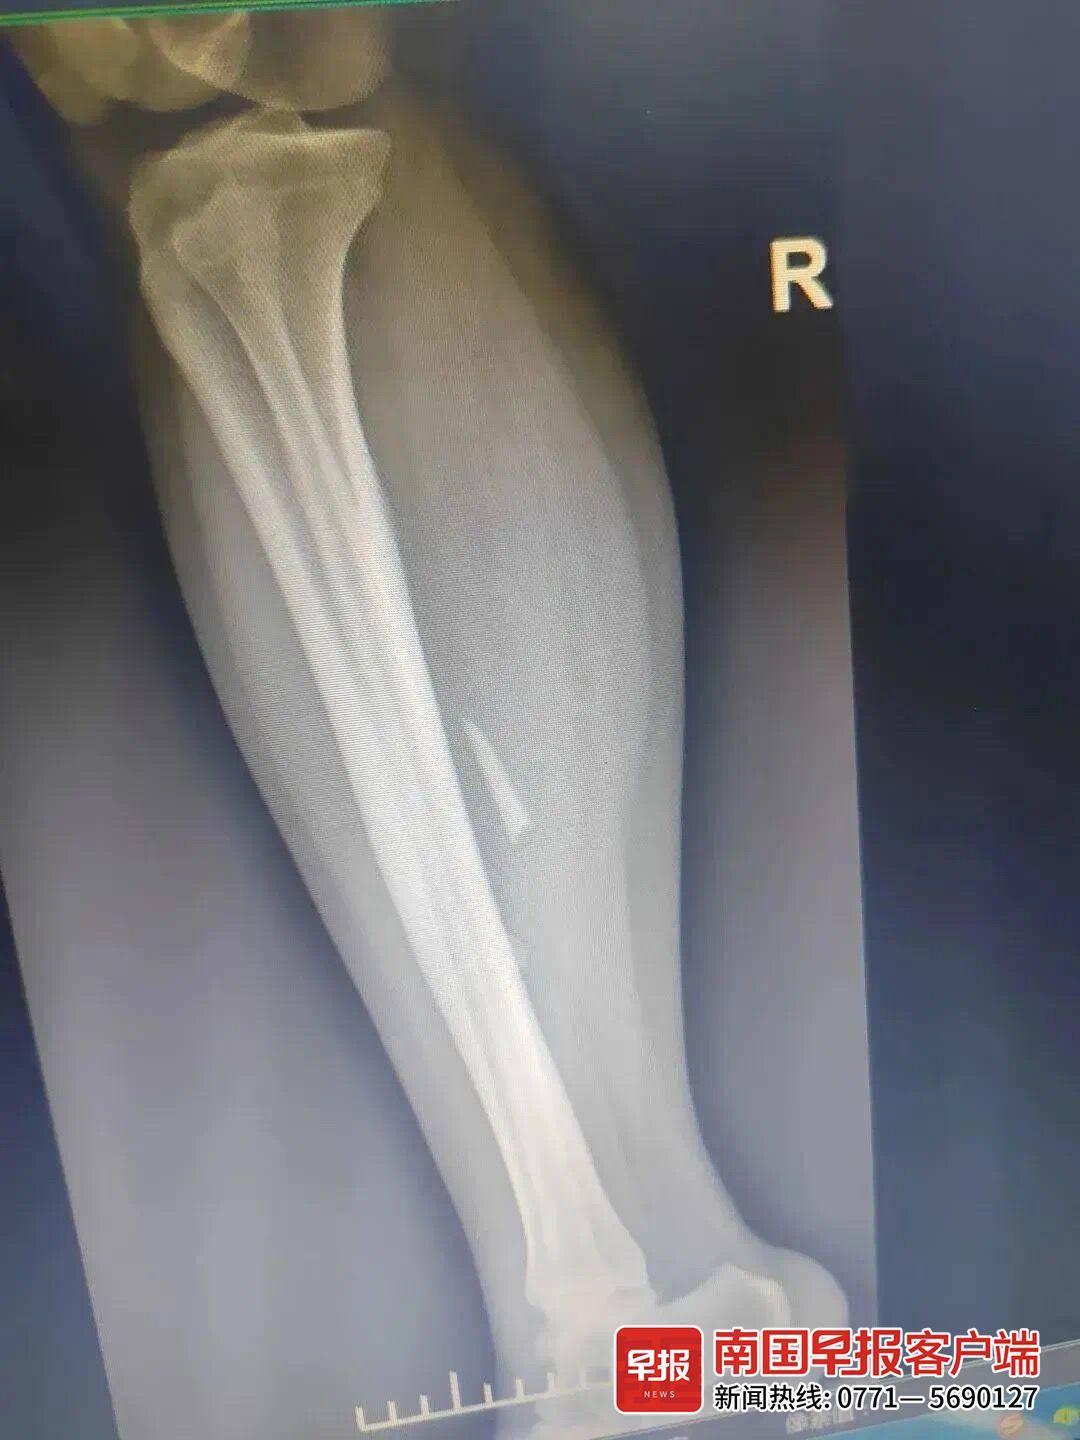

▲图为患者患处的影像资料。医院提供

今年29岁的小文患有多年的精神类疾病,几个月前,她总是叫嚷小腿痛,一开始家里人并没有放在心上。前段时间,为治疗小文的精神类疾病,家人带她到心理专科医院检查,并跟医生提及小文小腿疼痛一事。医生给小文拍片检查后发现,她的右侧小腿中段胫骨旁有异常密度影,疑似有异物残留。为进一步治疗,家人又带着小文到广西中医药大学附属瑞康医院就医。

瑞康医院创伤骨科与手外科副主任医师董盼锋给小文作了相关检查后发现,她右小腿异物的位置与原有瘢痕位置有一定距离,考虑异物进入体内后随着肌肉收缩发生了位移。

“异物已在体内存在两年多时间,与周围组织粘连较严重,必须更精准地给异物定位,清楚了解其与周围血管、神经的关系。”医生决定为小文进行肌骨超声定位。手术很顺利,在术前彩超定位下,医生很快就在小文的小腿肌肉中找到了异物:一块长约4厘米、厚约0.3厘米、顶部尖锐的锥形玻璃块。所幸玻璃并未伤及重要的血管神经,否则后果堪忧。异物取出后,大家都松了一口气。